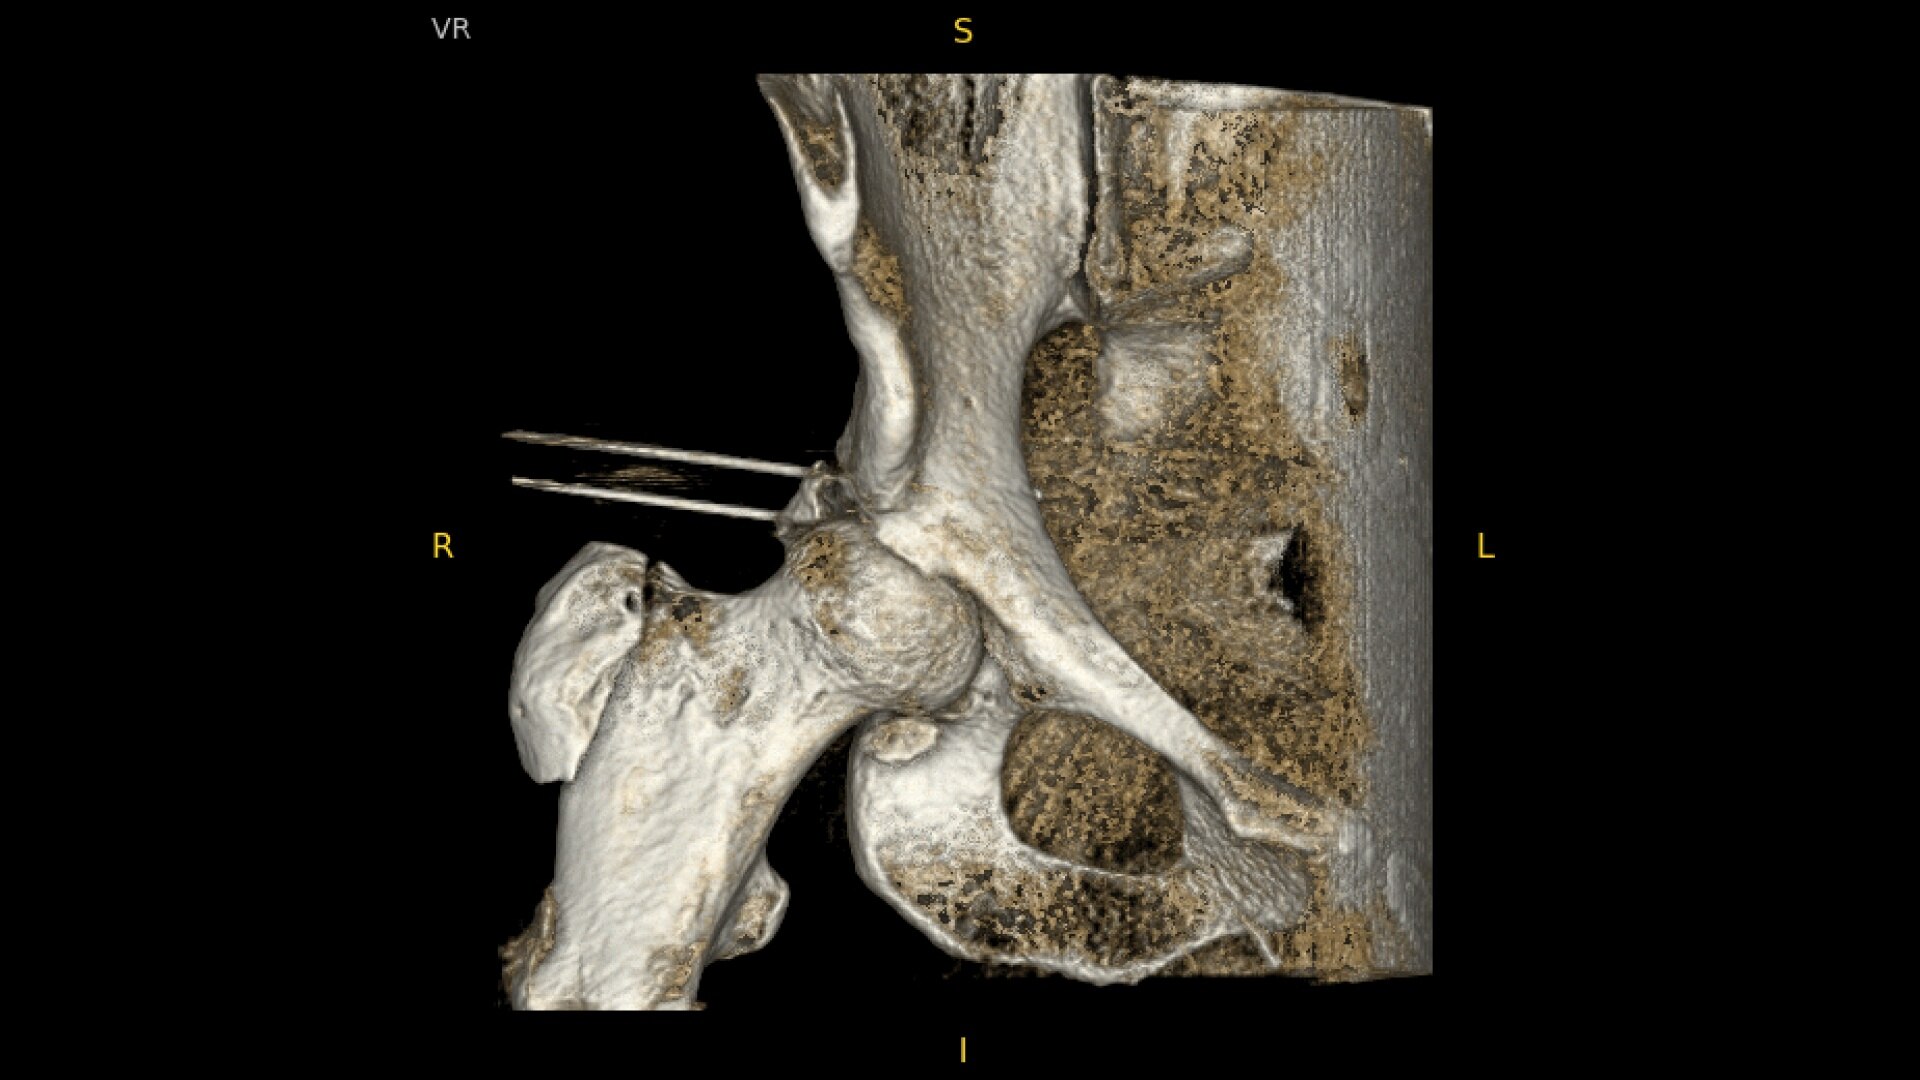

OEC C-arms provide orthopedic imaging with a large field of view optimized to clearly visualize orthopedic anatomy, such as the entire long bone femur or minute fractures in extremities. A clear display with comfortable viewing can easily show AP and lateral views, enabling efficient procedure planning.

See precise anatomical detail of varying densities such as bone and soft tissue with a high dynamic range with the OEC Elite CFD with a flat detector, image processing advancements and 4K viewing display.

Complex orthopedic procedures require powerful imaging systems. OEC premium C-arms perform in a variety of procedures such as:

• Hip fracture fixation

• Hip replacement